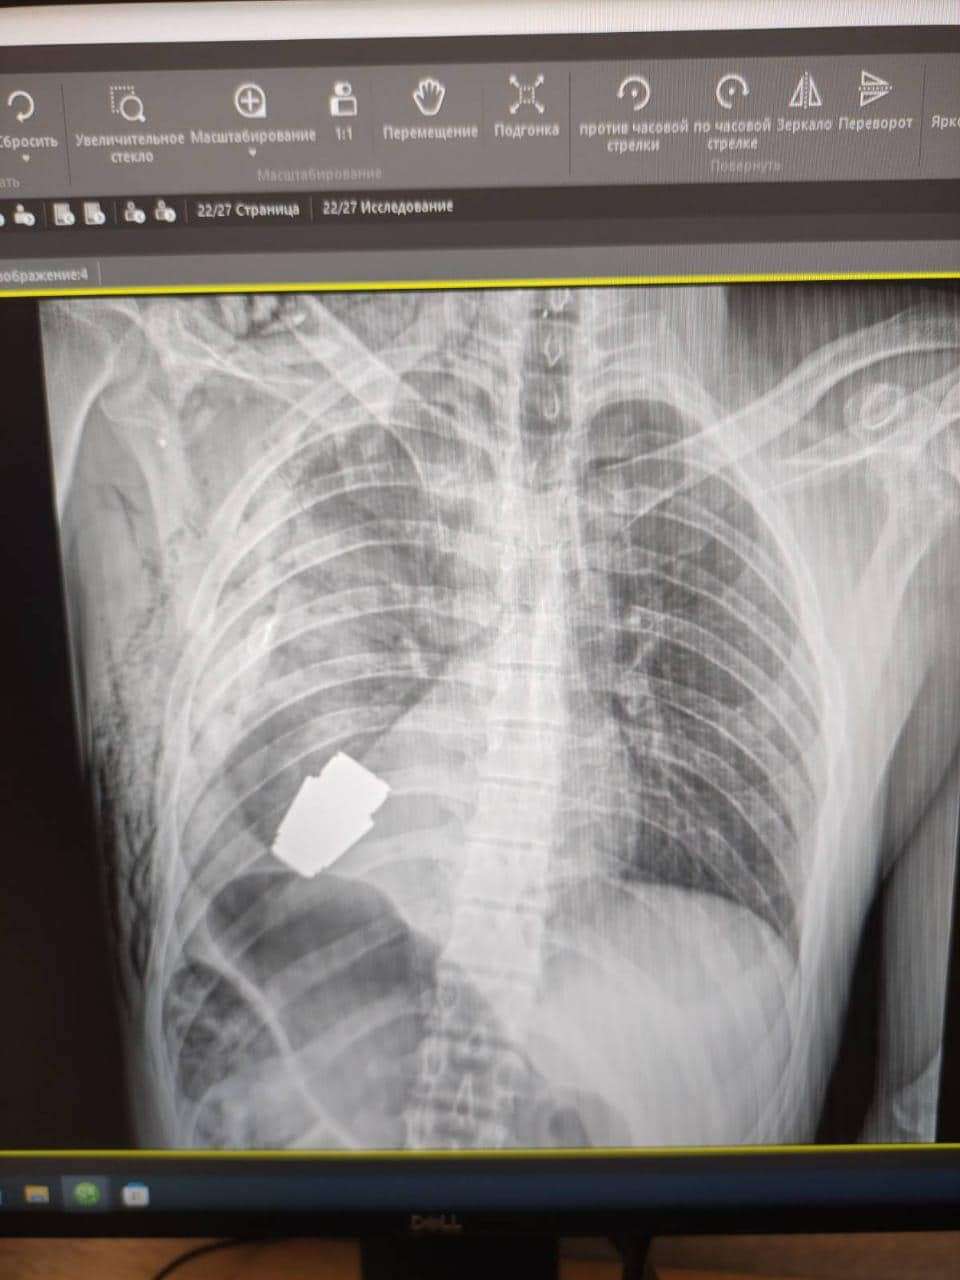

Операція під наглядом саперів: з тіла бійця ЗСУ дістали гранату, яка не розірвалася

Військові лікарі провели унікальну операцію  з видалення гранати ВОГ, яка не розірвалася, з тіла військовослужбовця.

Її було видалено у присутності двох саперів, які страхували безпеку медичного персоналу.

"Операція проводилася одним з найдосвідченіших хірургів ЗСУ - Андрієм Вербою без електрокоагуляції, оскільки граната могла детонувати у будь-який момент. Оперативне втручання пройшло успішно, а пораненого військовослужбовця було відправлено на подальшу реабілітацію та відновлення", - йдеться в повідомленні.